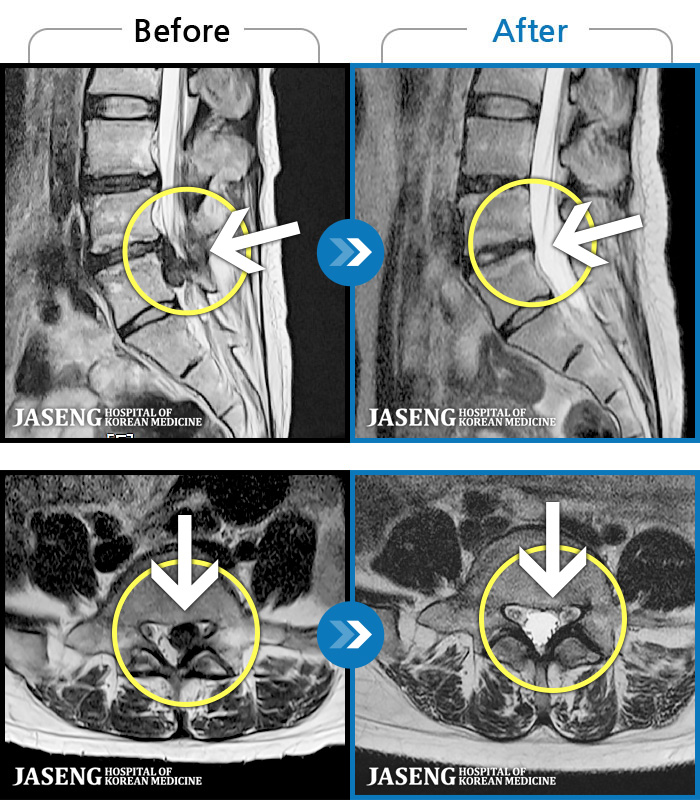

ȯںп Ǹ ǿ ԿǾ, ο ġ ۿ Ƿ ġḦ Ͻñ ٶϴ.